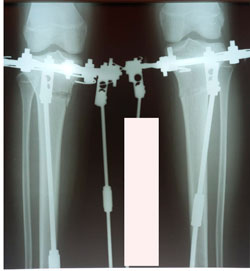

Исходник - 14 лет.

Дата операции - 16.12.2020

перед крутками

перед фиксацией

на фиксации

Дата снятия аппаратов - 17.02.2021